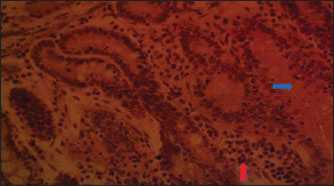

Fig. 4. (SNLM): Section of the intestine showing moderated necrosis of Crept of Lieberkühn (blue arrow) and mucosal (arrow head) epithelial cells, with infiltration of inflammatory cells (red arrow) (x400; H & E).

In the NLM shown in Figure 1, the mucosal lining was complete, with the Lieberkühn villi and crypts properly arranged. The epithelial layer, largely composed of absorptive enterocytes and goblet cells, was well preserved and did not show cellular erosion or necrosis (An et al., 2022). The lamina propria appeared to be free of inflammatory infiltrations, and the make-up was not atrophied or distorted, indicating a healthy mucosal barrier and optimum operational capacity (France and Turner, 2017). The TDLM (Fig. 2) had effects that showed cellular disintegration of the Lieberkühn crypts, signifying epithelial rejuvenation (Liu et al., 2019). At the same time, mucosal epithelial inner layer necrosis, shown by disturbed cellular structure and cytoplasmic degradation, suggests a distorted mucosal barrier that may amplify absorptivity, poor nutrient assimilation, and increased susceptibility to enteric pathogens (Chistiakov et al., 2014; De Medina et al., 2014). These observed changes can be due to the secondary metabolites like saponins, alkaloids, phenolics, and tannins present in Tithonia diversifolia, which are known to cause cytotoxic, anti-proliferative, and membrane-disrupting activities in the GIT tract when taken unprocessed (Abdelsalam and Fathi, 2023). These observations demonstrate the need for detoxification, quantification, and probably fermentation when incorporating TDLM into the diet of local rabbits (Abd-Elghany et al., 2021). Although TDLM provides a good source of nutritious and phytogenic benefits, its raw inclusion must be controlled to avoid compromising gut integrity and performance (Sugiharto et al, no date). In the observed PBLM in Figure 3, the necrosis in the crypt of Lieberkühn shows disturbance of the proliferative region crucial for epithelial regeneration and intestinal homeostasis (Chistiakov et al., 2014). Impairment of the crypts affects enterocyte production, which may cause weakened absorptive and digestive effectiveness in the small intestine (Buckley and Turner, 2018). Concurrently, mucosal epithelial cell degeneration and necrosis show intestinal barrier failure, increasing the danger of luminal antigen translocation and mucosal susceptibility (An et al., 2022). The permeation of inflammatory cells, mainly lymphocytes and macrophages, demonstrates a limited immune response that may be a reaction to epithelial injury caused by phytochemicals in Parkia biglobosa leaves (Franz et al., 2019). These bioactive constituents possess antioxidant and antimicrobial properties and may cause cytotoxic effects at high levels of inclusion in unprocessed form. Tannins and saponins can tamper with membrane integrity, modify gut microflora, and trigger mucosal irritation (De Medina et al., 2014). These effects are consistent with the inflammatory and degenerative changes observed in the duodenal mucosa (Chistiakov et al., 2014; De Medina et al., 2014). The observed necrosis in the crypt that controls epithelial cell production and mucosal renewal in rabbits fed SNLM indicates weakened cellular turnover (Buckley and Turner, 2018). Moreover, the loss of mucosal epithelial cells’ integrity shows that the absorptive and protective barrier is compromised, which is crucial for nutrient uptake and host protection (Liu et al., 2022). The infiltration of inflammatory cells, principally comprising lymphocytes and plasma cells, into the lamina propria, as shown in Figure 4, demonstrates an ongoing immune response that may have been prompted by mucosal or antigenic disturbance from biologically active compounds in Synedrella nodiflora. If the concentration is not regulated, this can lead to a cytotoxic or pro-inflammatory effect on the mucosa of the GIT (Jha et al., 2019). Specifically, saponins are known to disrupt membranes and increase gut penetrability, possibly leading to reactionary inflammation and epithelial damage (Ohimain et al., 2020). Necrosis of the Lieberkühn crypt observed in the LMM (Fig. 5) and damage to the mucosal epithelial cells affect the intestinal epithelium, compromising absorptive and secretory activities crucial for gut health (Buckley and Turner, 2018). This pattern is consistent with that observed in other leaf meals; however, the infiltration of inflammatory cells appeared mild, suggesting a moderate but continuous controlled immune response, possibly to clear away cellular fragments and restore mucosal integrity (Chistiakov et al., 2014; De Medina et al., 2014). This trend aligns with subacute intestinal damage, where soreness is present but not distressing, enabling mucosal recovery if the injurious stimuli are removed (France and Turner, 2017; An et al., 2022).